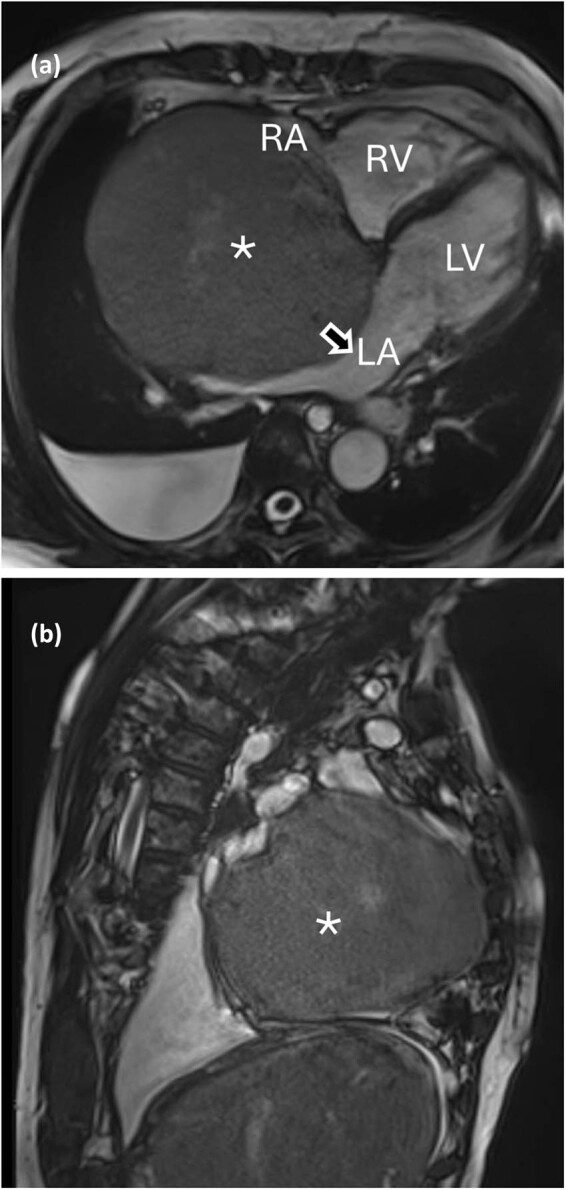

Methods: We report herein the case of a 72-year-old woman with a giant right atrial mass. The patient suffers from abdominal swelling related to ascites. The histological examination of the tranjugular biopsy suspected an atrial myxoma.

Results: The patient was scheduled for surgical excision of the cardiac tumour. Radical resection of a 13 cm mass was performed. The histological diagnosis revealed cardiac hemangioma.

Conclusion: Cardiac hemangiomas can rarely grow larger than 5 cm, cause few symptoms, and are easily confused with atrial myxomas. Hepatomegaly and ascites may be signs of cardiac hemangioma.